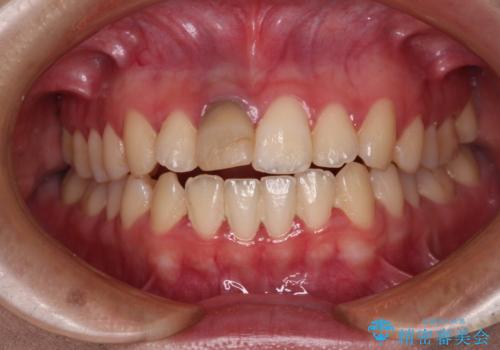

茶色になった前歯 オーダーメイドタイプのオールセラミッククラウン

- 虫歯により神経を取り除いた前歯の変色が気になるとのことで来院された患者様です。

レントゲン写真より、歯根の炎症が認められなかったため、ファイバーコアによる土台築製後、オーダーメイドタイプのオールセラミッククラウンにて補綴することとしました。